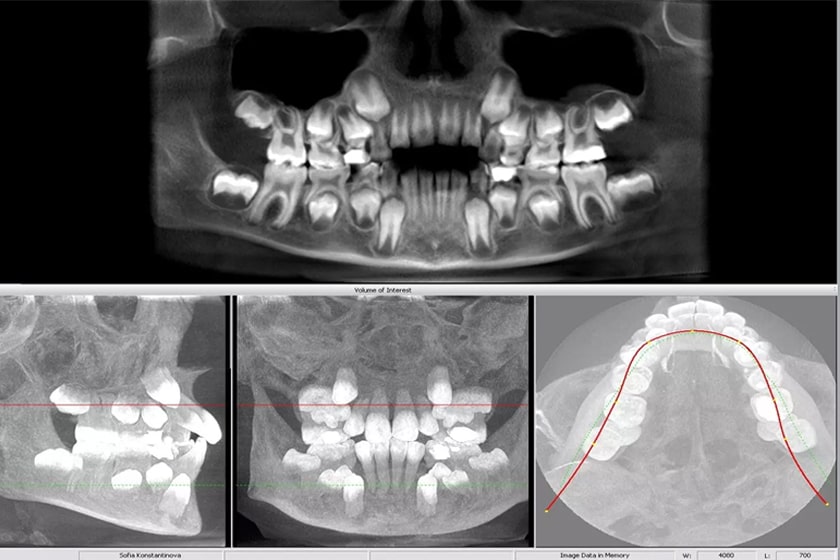

Рентгенография – один из самых доступных и информативных методов исследования костной ткани. Она позволяет выявить широкий спектр патологий, от переломов до опухолей и дегенеративных изменений. Однако правильная интерпретация рентгеновских снимков требует определенного опыта и знаний. В этой статье мы подробно рассмотрим, как оценивается состояние костной ткани на рентгенограммах, какие признаки указывают на различные заболевания, и какие дополнительные методы исследования могут потребоваться для уточнения диагноза. Подробное понимание этого процесса поможет вам лучше ориентироваться в результатах обследования и обсуждать их с вашим лечащим врачом.

Рентгеновские лучи позволяют визуализировать костную ткань благодаря разнице в плотности кости и окружающих мягких тканей. Здоровая костная ткань на рентгенограмме выглядит однородной, с четкими контурами и нормальной архитектурой. Изменения в структуре, плотности или форме кости могут свидетельствовать о наличии патологического процесса. Анализ рентгеновских снимков включает в себя оценку нескольких ключевых параметров⁚ плотности костной ткани, структуры кости, наличия переломов, деформаций и других аномалий.

Рентгенография, хотя и является ценным инструментом, не всегда позволяет получить полную информацию о состоянии костной ткани. В некоторых случаях могут потребоваться дополнительные методы исследования, такие как компьютерная томография (КТ), магнитно-резонансная томография (МРТ) или денситометрия. КТ обеспечивает более детальное изображение костной ткани, чем рентгенография, а МРТ позволяет визуализировать как костную ткань, так и окружающие мягкие ткани. Денситометрия используется для оценки плотности костной ткани и диагностики остеопороза.